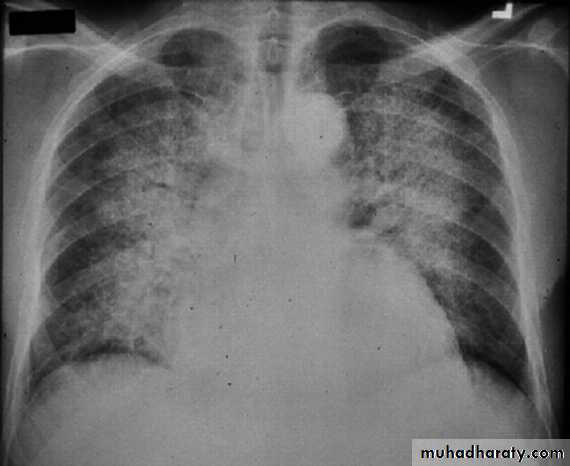

BNP brain natriuretic pepetideChest X-ray in Heart Failure

CardiomegalyCephalization of the pulmonary vessels

Kerley B-lines

Pleural effusions

Cardiomegaly Pulmonary vessel congestion